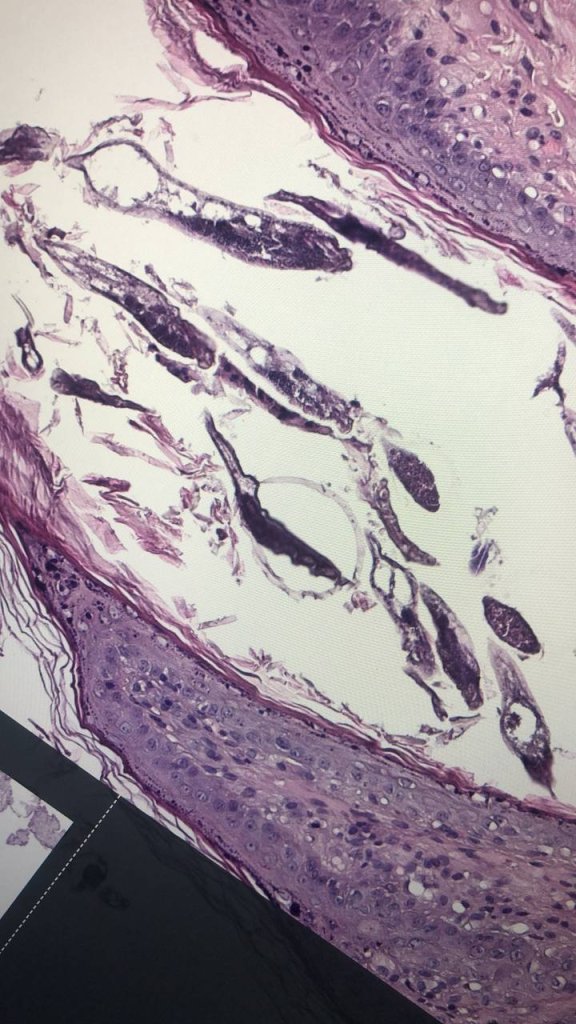

Редкая нынче находка, особенно в гистологических препаратах....

Редкая нынче находка, особенно в гистологических препаратах. Клещи рода Demodex